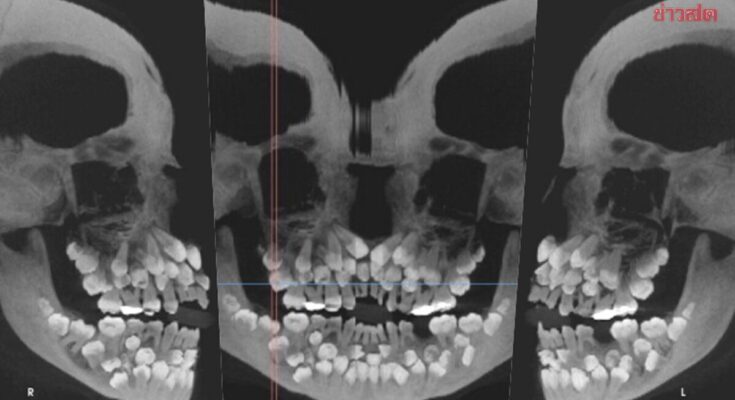

เด็กหญิงคนหนึ่งอายุ 11 ปี 8 เดือนในเมืองมีนัสเชไรส์ ประเทศบราซิล ได้เข้ารับการตรวจสุขภาพช่องปากที่คลินิกทันตกรรม เนื่องจากเธอวางแผนที่จะถอนฟันน้ำนมแถวบนที่ยังไม่หลุด อย่างไรก็ตาม ภาพเอกซเรย์เผยให้เห็นการค้นพบที่น่าตกใจ นั่นคือ จริง ๆ แล้วเธอมีฟันน้ำนม 18 ซี่ ฟันแท้ 32 ซี่ และฟันเกินอีก 31 ซี่ในช่องปาก รวมเป็นฟันทั้งหมด 81 ซี่

จากการตรวจในช่องปาก แพทย์บันทึกไว้ว่ามีเพียงฟันแท้ 5 ซี่ที่งอกออกมาแล้ว ในขณะที่ฟันน้ำนมยังคงมีอยู่จำนวนมาก เพื่อประเมินสภาพฟันและช่องปากของผู้ป่วยเด็กให้ครบถ้วนมากขึ้น แพทย์จึงสั่งให้ถ่ายภาพเอกซเรย์แบบภาพรวมและภาพกะโหลกศีรษะด้านข้าง

อีกทั้งภาพเหล่านี้ยังแสดงให้เห็นว่าฟันหลายซี่มีรูปร่างผิดปกติ ฝังลึกอยู่ในเหงือก ทำให้การแยกแยะระหว่างฟันปกติและฟันส่วนเกินเป็นเรื่องที่ยากลำบากอย่างมาก ซึ่งผู้ใหญ่ทั่วไปควรมีฟัน 32 ซี่ และฟันที่เกินมานี้เรียกว่า “ฟันเกิน” โดยทั่วไปจะมีฟันเกินเพียง 1 – 2 ซี่เท่านั้น